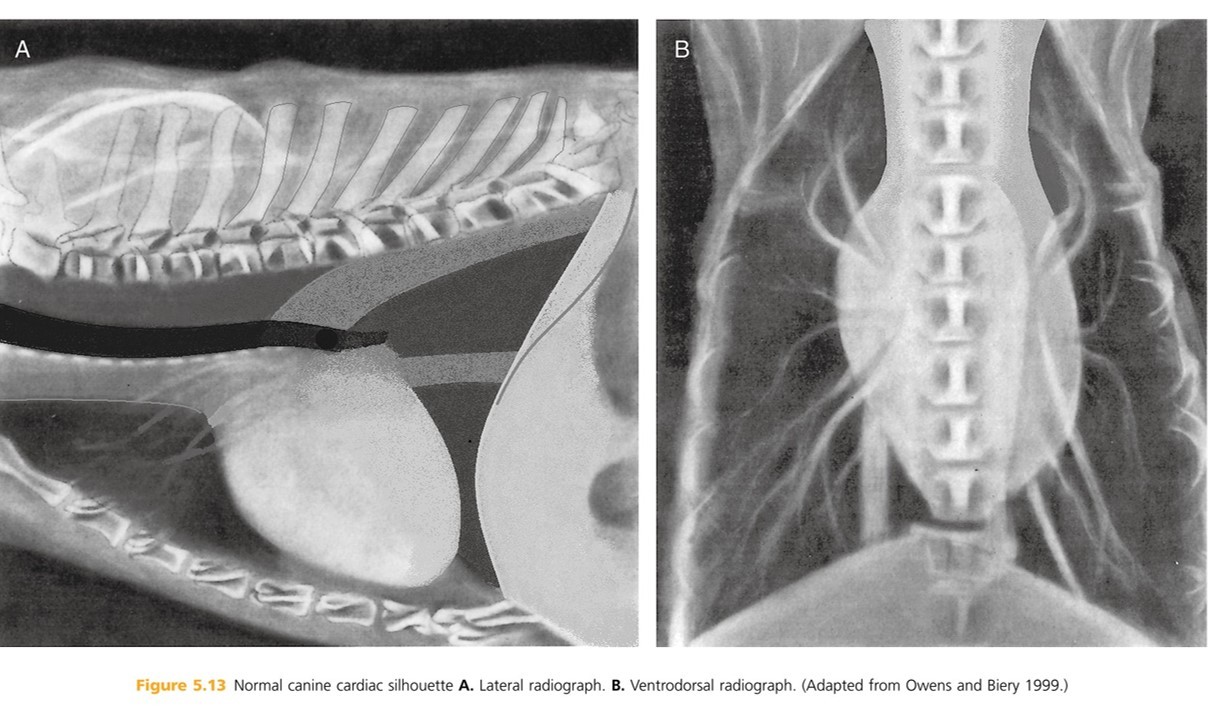

Heart: The shadow is actually the pericardium and the heart should be termed the cardiac silhouette. The cardiac silhouette fills about 3/4 of the thorax in a lateral view and 2/3 in a DV/VD view. Minimal heart enlargement will be hard to determine. The heart appears as a solid globe, so the boundaries are evaluated rather than the chambers. The cardiac silhouette should be less than half the width of the VD thorax at the level of the ninth rib.

The heart is obliquely positioned in thoracic cavity:

Lateral rad- long axis is approximately 45 degrees to perpendicular

Ventrodorsal rad- long axis is approximately 30 degrees to spine

The base of the heart is located at the ___ or ___ intercostal space. What does the heart base include? The tracheal bifurcation (coarina) is dorsal to base of the heart, approximately ____ % of the distance from sternum to spine.

5th or 6th

atria, ascending aorta, portions of pulmonary trunk, cranial vena cava

70%

The apex of the heart is formed by the _______ ______.

Lateral radiographs the apex is angled _______.

interventricular sepum

caudoventrally (back and down)